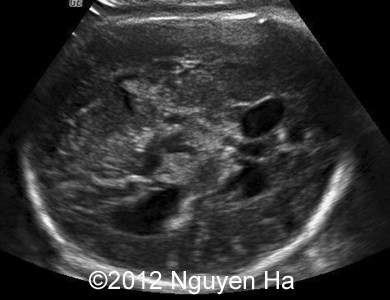

A 30-year-old woman (G1P0), with unremarkable family history, presented to our unit at 36 weeks of her pregnancy. She did not undergo any previous screening tests. Our examination (and repeated scan after four days) revealed following findings:

Figures 1-7: 36 wekks of pregnancy.

A 30-year-old woman (G1P0), with unremarkable family history, presented to our unit at 36 weeks of her pregnancy. She did not undergo any previous screening tests. Our examination revealed unilateral hypoechoic inhomogeneous mass within cerebral parenchyma. Our initial diagnosis was teratoma, but repeated exam after four days showed structural changes and different echogenicity of the mass and so our final diagnosis was cerebral hemorrhage. The findings were confirmed by MRI scan.

Figure 1-7: 36 wekks of pregnancy.